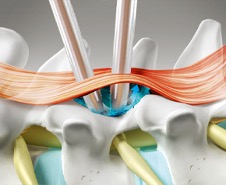

소위 디스크라고 잘 알려진 추간판탈출증은 척추뼈와 척추뼈 사이에 존재하는 추간판(디스크)이 어떤 원인에 의해 손상을 입으면서내부의 수핵이 밖으로 밀려 나와 주위 조직, 특히 척추신경을 압박하면서 통증 등의 증상을 유발하는 질환입니다.

안정과 휴식을 취하면서 약물치료, 주사치료, 운동치료, 도수치료, 체외충격파 등을 복합적으로 시행합니다. 비수술치료시 신경차단술, 신경성형술, 협착부위 풍선확장술 등을

통해 질환을 호전시 킵니다.

비수술 치료에도 증상이 호전되지 않거나 보행 장애가 심각한 등 일상생활에 지장이 있다면 수술 치료를 시행하하며 양방향척추내시경 및 미세현미경레이져수술,

척추유합술 등을 통해 치료합니 다.